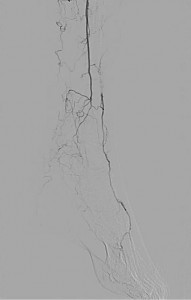

There was a severe stenosis of the left tibioperoneal trunk (Figure 2) and single vessel runoff to the foot via the left peroneal artery (Figure 3):